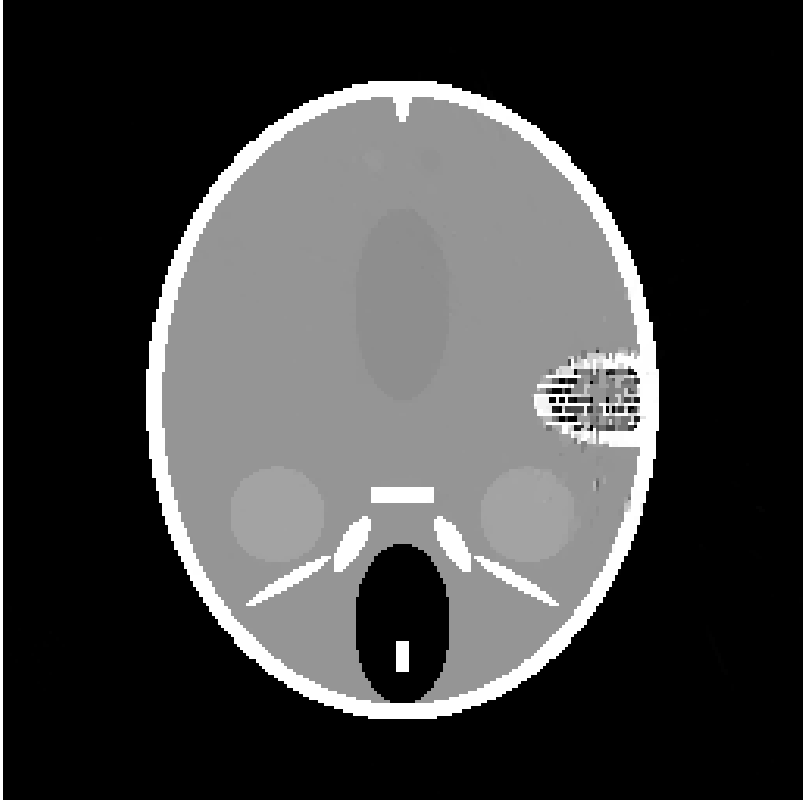

In this section we report the results of several tests run on simulated under-sampled data obtained by synthetic (phantoms) and full resolution MRI images. The under-sampled data are obtained as where is the full resolution image and is the under-sampling Fourier matrix, obtained as in (5). The under-sampling masks, analyzed in the next paragraphs are: radial mask (), parallel mask () and random mask (). In figure 1 we represent an example of each mask with low sampling rate , measured by the percentage ratio between the number of non-zero pixels and the total number of pixels :

| (48) |